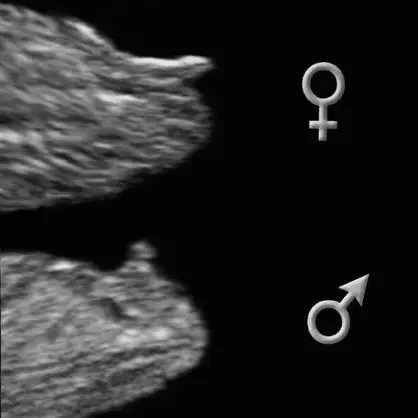

dr soylemeden siz gorun genital nub teorisi ( bebegin cinsiyeti)

Canım bak bu orkıde hanımın koydugu foto yukardakı kız bebek ve benım foto aynı ona benzıyor ama : ) kırmızı gıbı olanlar benım fotom dıgerlerı orkıde hanımın kız bebek dıye koydugu fotolar bı bakabılırmısın..ayrıca arkadaslar anlayanlar benım fotomada yorum yapıverın rıca edıyorum lutfen lutfen lutfen :)

En sondakı foto da orkıde hanımın koydugu erkek fotosu nubu nasıl yukarda benımkı paralel gelıyo gıbı